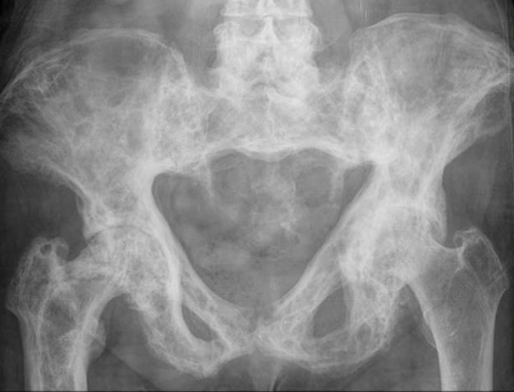

Xray

Findings

- mixed lysis and sclerosis

- cortical thickening

- bone expansion and deformity

Pelvis

Coxa vara / protrusio / OA